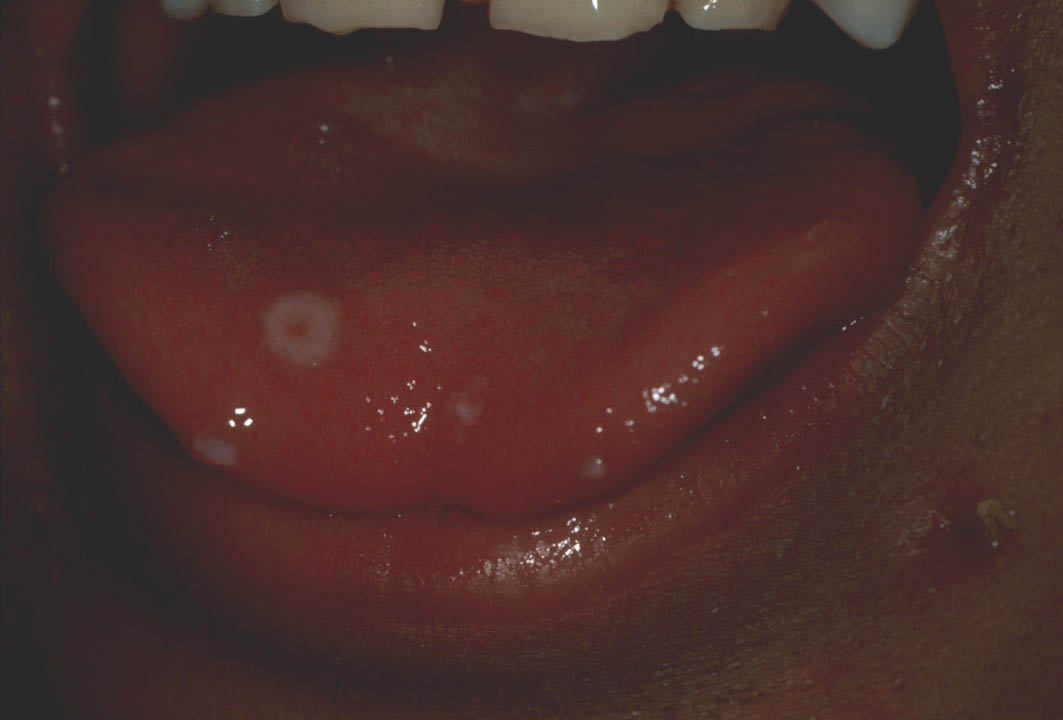

Varicela - varsat de vant (infectie contagioasa)